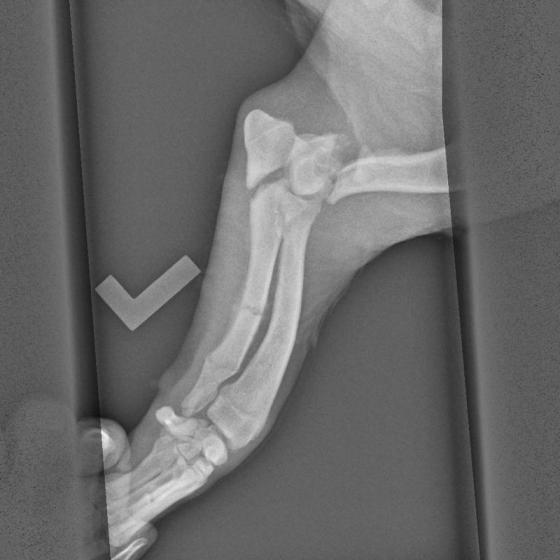

Skip bol nájdený 7. mája 2015 v jarku medzi Veľkým Mederom a Dolným Štálom, mal šťastie, pretože práve na tejto ceste je jarok veľmi hlboký, Skip sa ale vyplazil na cestu a hľadal pomoc. Ihneď sme ho naložili do auta a utekali sme s ním k nášmu pánovi doktorovi, keďže nám bolo jasné, že to nebude iba udretie, čo musíme riešiť, Skip nám pod rukami pukal pri každom dotyku a odovzdane nám pozeral do očí, vedel, že už bude dobre, že mu pomôžeme. Išli sme najprv na RTG, celú dobu sa nechal polohovať a pozeral nám pri tom do očí, zmierený s osudom, zrejme si povedal, že viac, ako to bolí, to už bolieť nebude. Z prvých snímkov je viditeľné, že má zlomený lakeť ľavej prednej nohy a aj kosti tam má polámané, takisto má zlomenú ľavú zadnú nohu, panva zatiaľ zlomeninu neukázala, ale uvidí sa pri podrobnejšom vyšetrení v pondelok, kedy pôjde na operáciu. Faktom však je, že to nebolo úplne čerstvé zranenie, takže v tej priekope ležal už niekoľko dní, ten, čo ho zrazil, ho tam bezcitne nechal napospas osudu a Skip v bolestiach čakal na smrť.